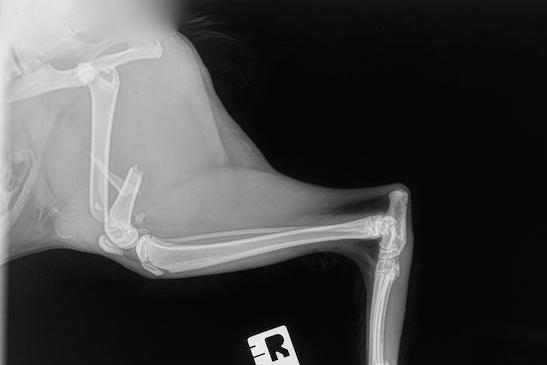

Diagnostic des fractures chez les chats et chiens

L’examen physique et orthopédique permet d’orienter le diagnostic. Une boiterie soudaine, une enflure marquée, une instabilité articulaire et une douleur intense sont des signes évocateurs. La radiographie est l’outil principal pour confirmer la fracture. Plusieurs clichés sont nécessaires pour obtenir une vue en trois dimensions de l’os. Dans certains cas complexes, un scanner peut être recommandé pour une évaluation plus précise.